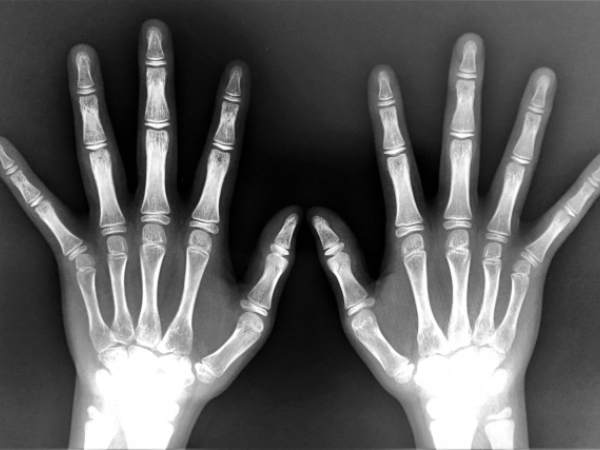

そうすると、体内のカルシウムとリンのバランスが乱れ、血管が固く脆くなる石灰化のリスクにさらされます。

また、ラットの研究では、無機リンの多い餌を与えると、腎臓の石灰化が進み(腎機能低下)、食欲低下や体重減少が見られたという報告(※)もあります。

今回取り上げている“無機リン”の摂りすぎは、カルシウムの吸収が阻害されるため骨粗鬆症のリスクが指摘されています。